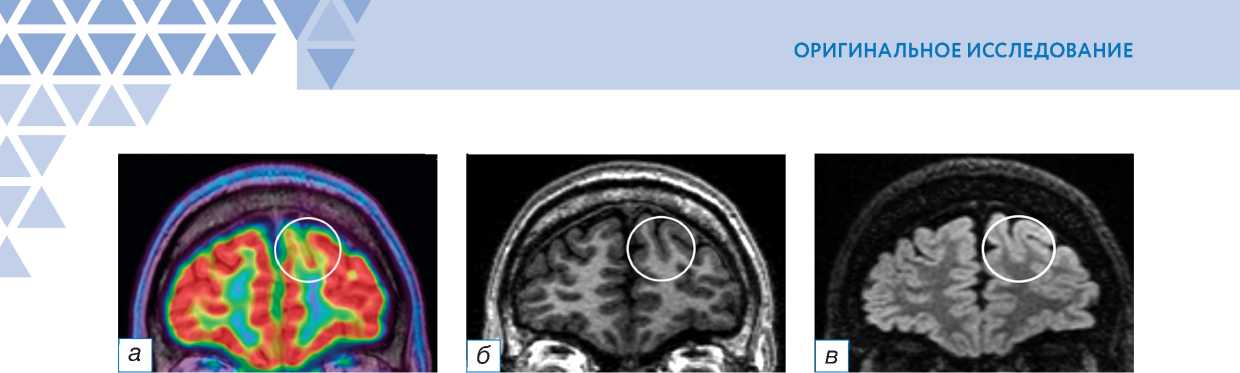

ФКД выявлена у 13 (56,5%) пациентов с помощью МРТ, у 22 (95,6%) — с помощью гибридного исследования ПЭТ/МРТ с 18F-ФДГ, из них 6 (26,1%) пациентов были МР-негативными, в 3 (13%) случаях признаки ФКД обнаружены на изображениях МРТ при повторном прицельном анализе изображений в зоне гипометаболизма 18F-ФДГ (рис. 1). В одном МР-негативном случае зона гипометаболизма 18F-ФДГ выявлена ретроспективно при пересмотре изображений ПЭТ/МРТ после инвазивного ЭЭГ-ВМ.

Рис. 1. Совмещённая позитронно-эмиссионная томография с магнитно-резонансной томографией (ПЭТ/МРТ) головного мозга с 18F-ФДГ пациента с фокальной кортикальной дисплазией дна борозды в левой лобной доле: а (совмещённое изображение ПЭТ/МРТ в корональной плоскости) — участок гипометаболизма 18F-ФДГ в области фокальной кортикальной дисплазии (окружность); б (Т1-ВИ в корональной плоскости) — небольшой участок снижения серо-белой демаркации в области дна борозды в левой лобной доле (окружность); в (Т2-FLAIR в коро-нальной плоскости) — небольшой участок повышения интенсивности МР-сигнала и снижения серо-белой демаркации в области дна борозды в левой лобной доле (окружность); г (Т2-ВИ в аксиальной плоскости) — небольшой участок снижения серо-белой демаркации в области дна борозды в левой лобной доле (окружность); д (гистологический препарат, окраска гематоксилином и эозином, х400) — дисморфичные нейроны.